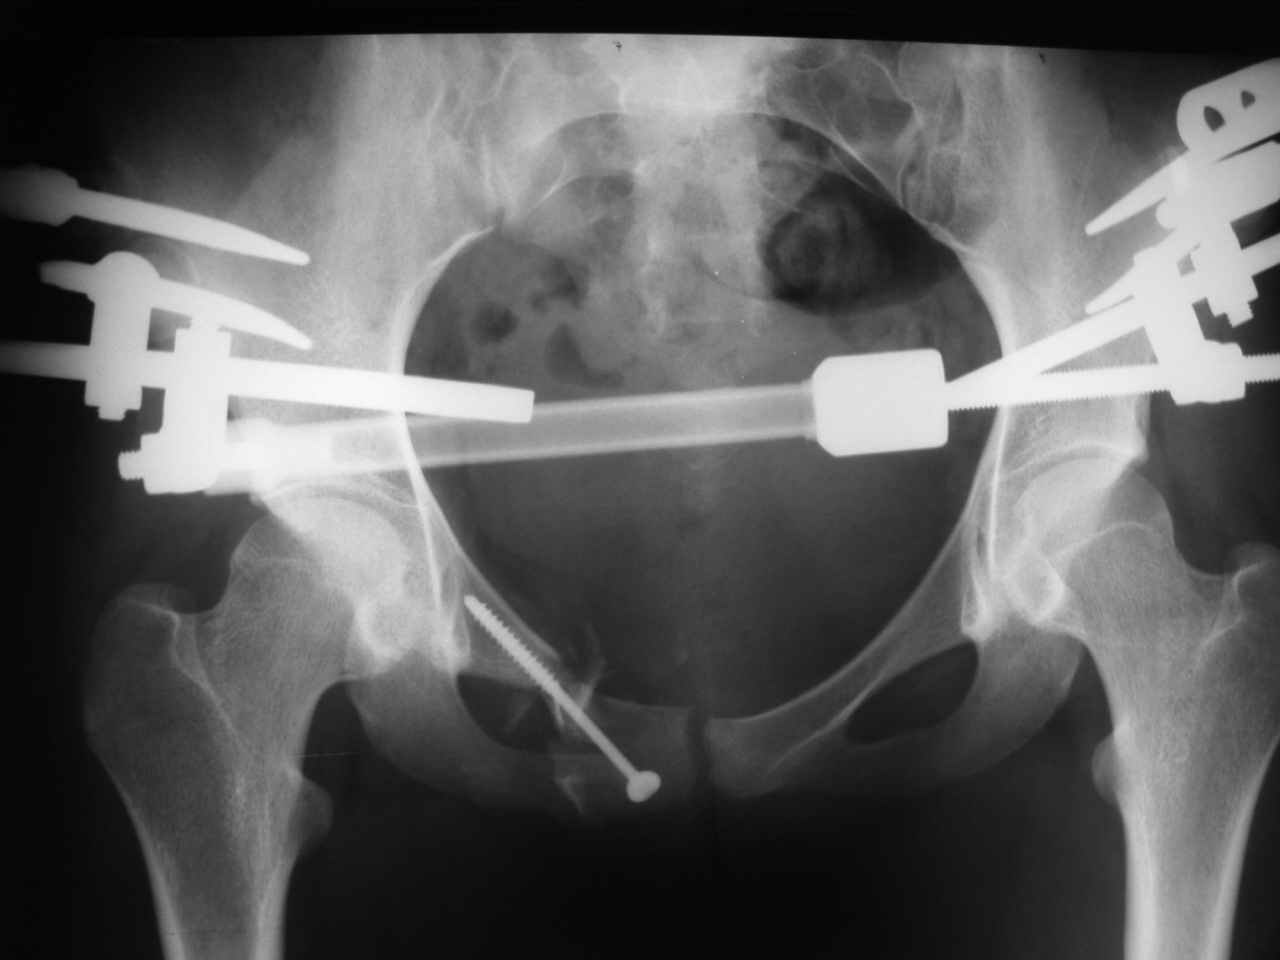

Вот на этом думаю и остановится. А надо ли вообще фиксировать ротационное повреждение задних отделов винтами (тем более через месяц)? Было бы вертикальное, то тут без вопросов!